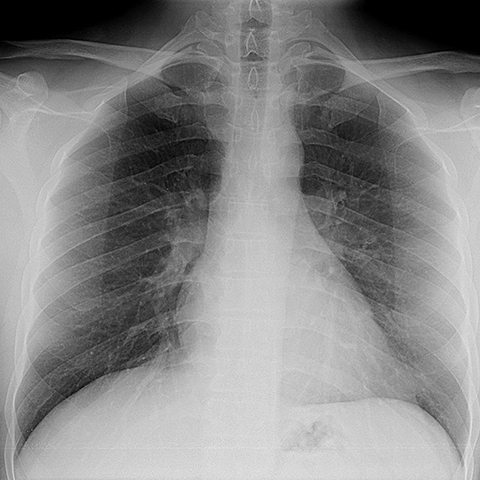

Normal AP Chest Radiograph [2 of 2]